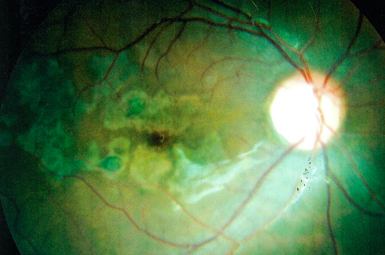

Macular Edema (CME)

Many eye conditions lead to macular swelling. Treatments include intravitreal injections, laser photocoagulation, periocular injections, and occasionally vitrectomy surgery.

Diabetic Retinopathy

Fifty percent of patients with Diabetes for 10 years exhibit some level of eye involvement. Aggressive treatment usually preserves vision.

Retinal Vascular Occlusion

Arteriosclerosis can lead to retinal blood flow problems and impaired vision. Injections, laser, and/or surgery frequently improve vision.